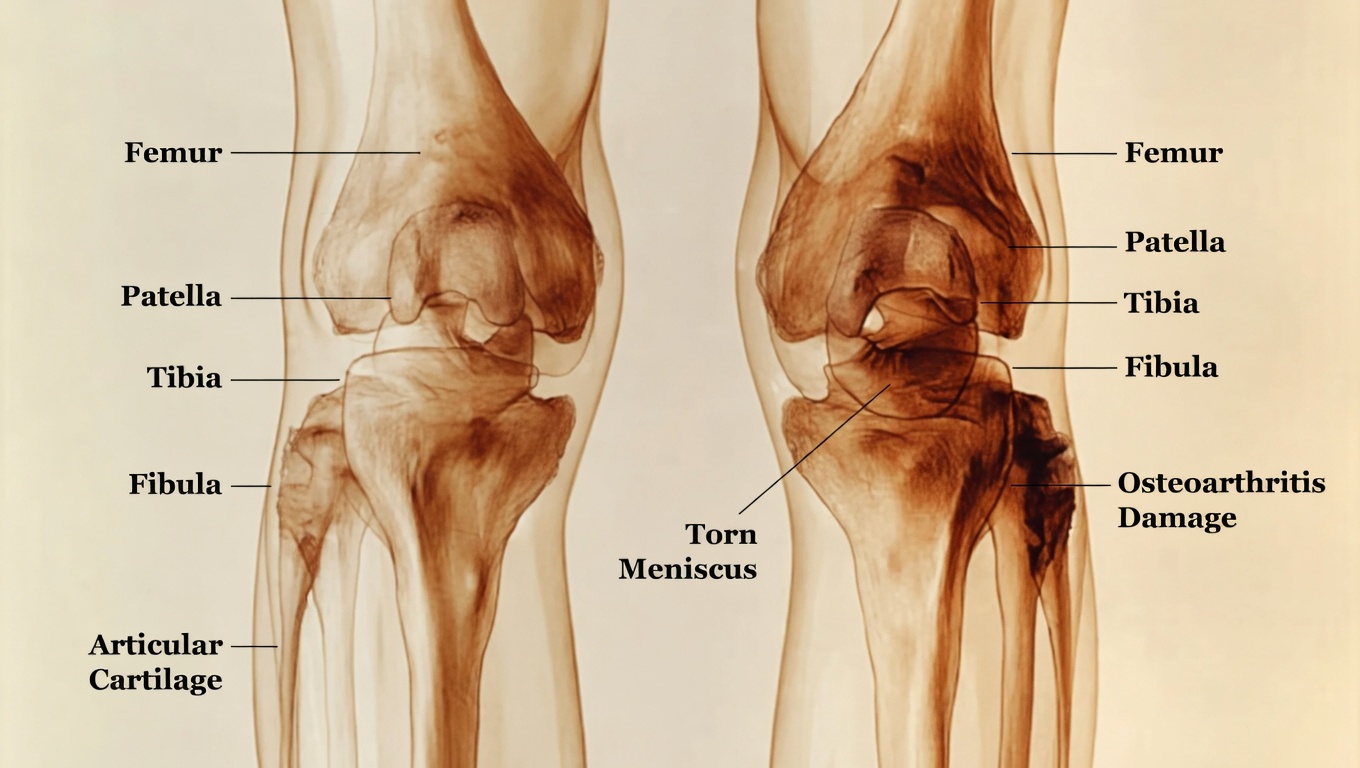

The story does not end with calcium and bone health. Muscles also rely on vitamin D to help regulate contraction and support normal inflammatory responses. When vitamin D is too low, the body may respond with the kind of aching that settles into the knees, shins, hips, or ankles.

Institutions such as Cleveland Clinic and Yale Medicine have noted that vitamin D influences both skeletal health and everyday physical comfort. That helps explain why a deficiency may show up not only as bone tenderness, but also as muscle weakness, soreness, or reduced mobility.